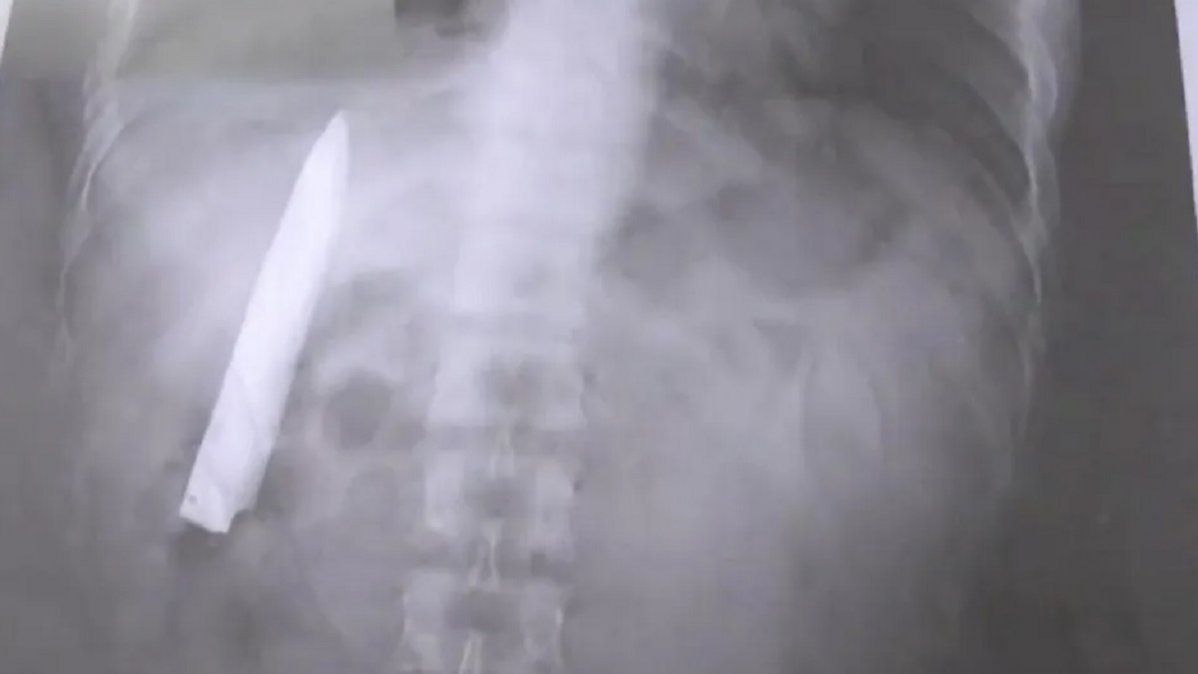

Lo apuñalaron y 14 meses después le encontraron un cuchillo en el pecho

Un hombre de Filipinas descubrió que tenía una hoja de cuchillo dentro de su torso 14 meses después de haber sido apuñalado por un grupo de adolescentes en la ciudad de Kidapawan.

El filipino, de 25 años, se percató de la negligencia cuando asistió el 23 de marzo a un hospital para realizarse pruebas de rayos X, requerimiento para postular a un nuevo trabajo en la provincia de Agusan del Sur.